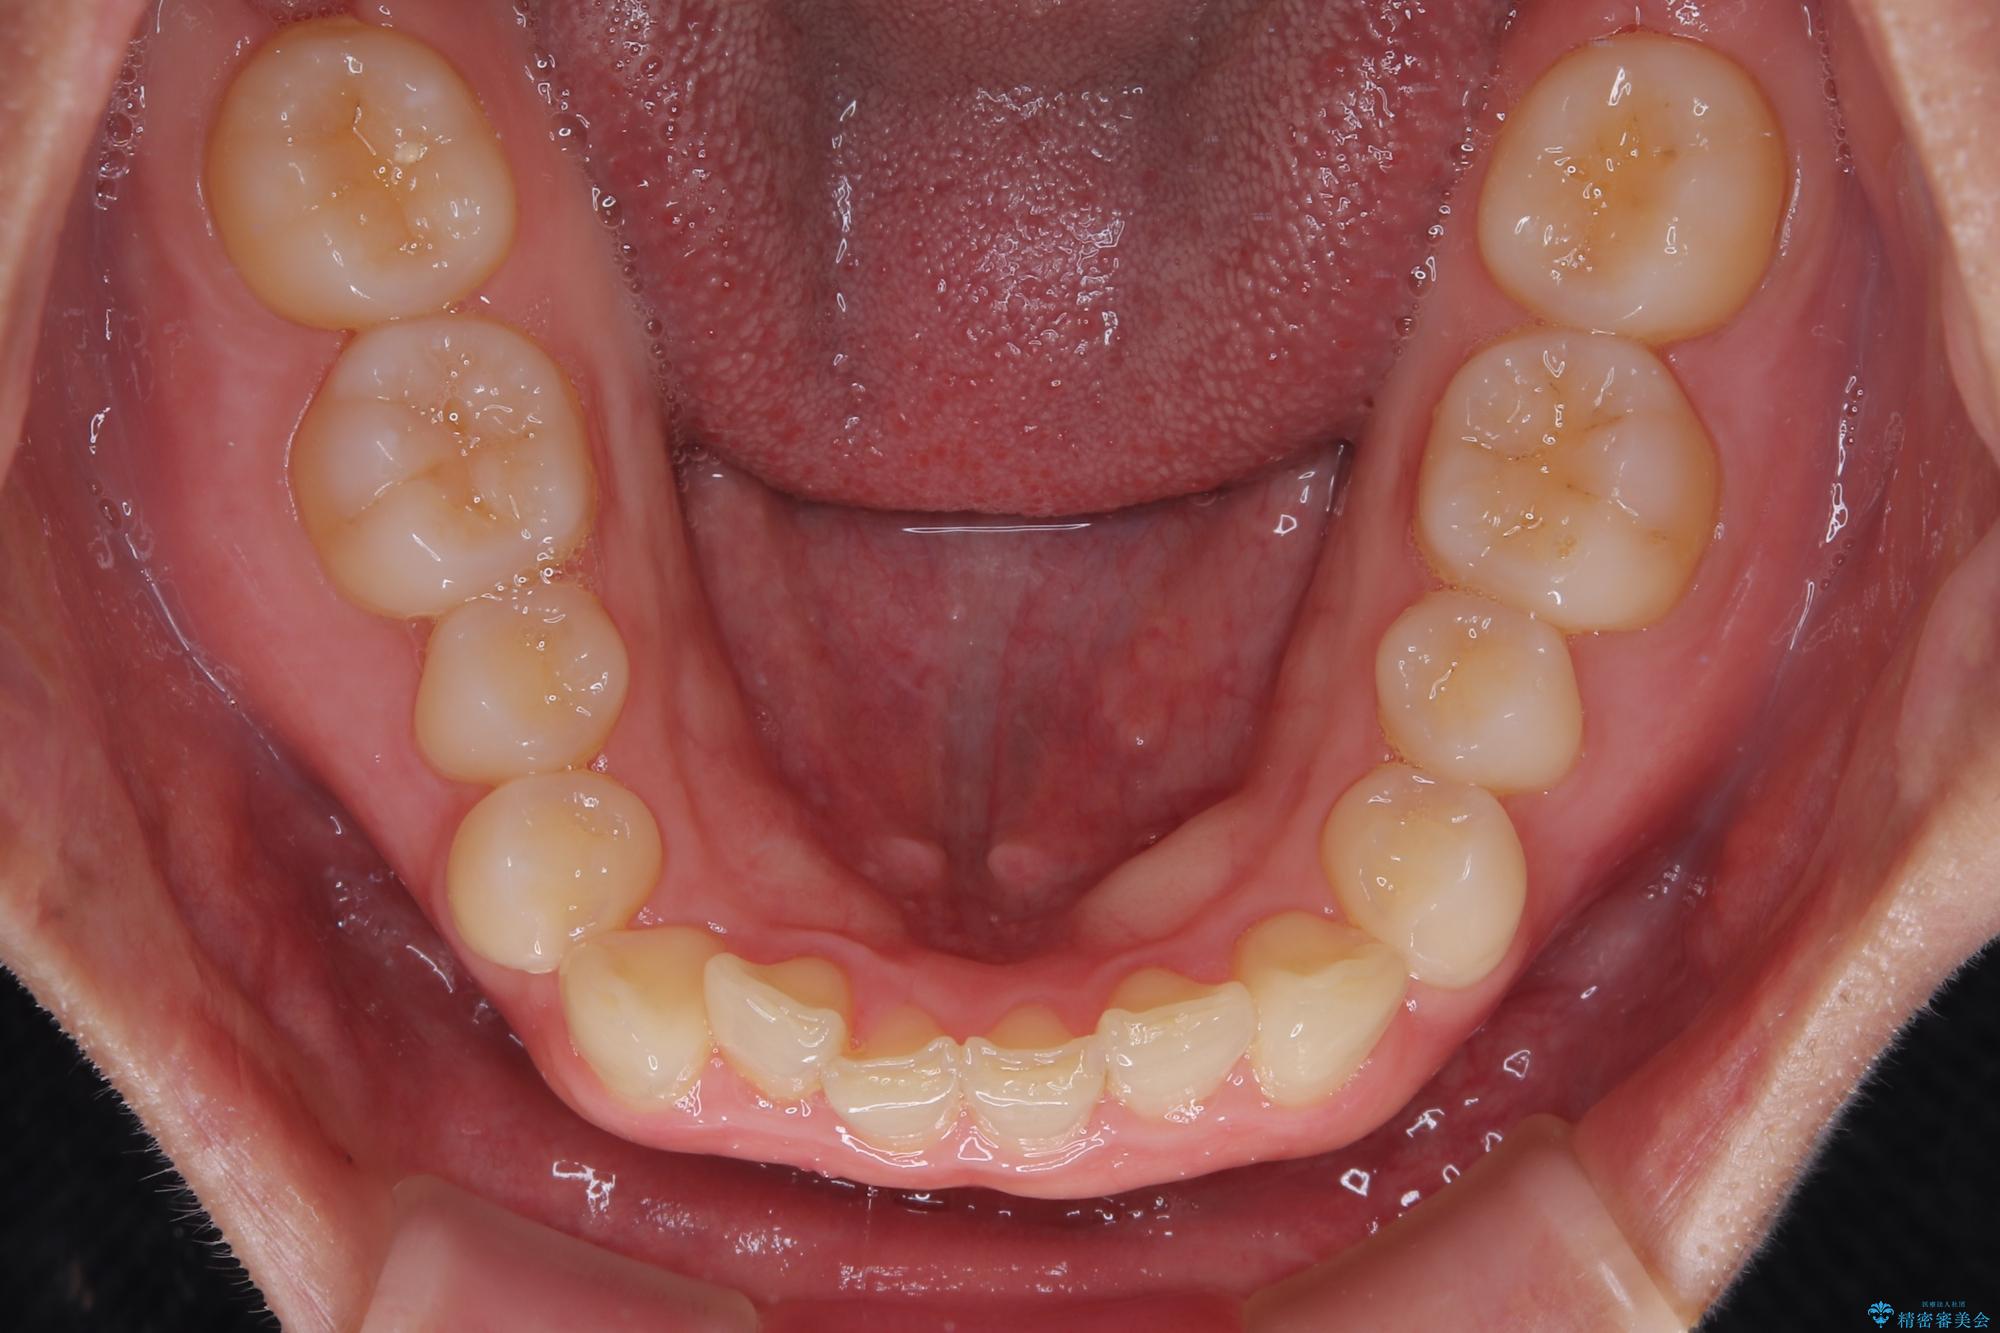

- 下顎前歯が完全に隠れてしまっていることを気にして来院された患者様です。

下顎の臼歯が手前に傾斜していることで咬み合わせが深くなってしまい、下顎前歯が見えないほどに上顎前歯が覆い被さっている状態でした。

下顎臼歯を起き上がらせるためにユーティリティーアーチを使用し、一気に深い咬み合わせを改善することができました。